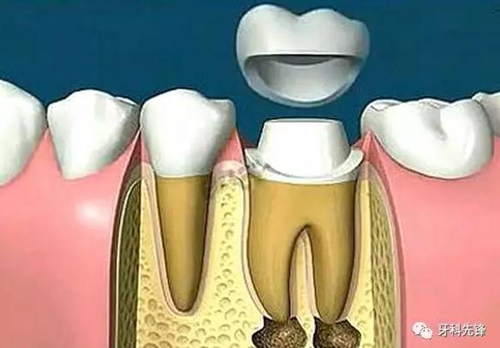

根管治療后需要做牙冠,原因有三

1、因為需要進行根管治療的牙齒,一般已經(jīng)是蛀牙缺損很大,這個時候雖然根管治療完成,但是剩下的牙體組織非常脆弱,容易折斷、裂開,失去正常的功能,單純用材料已經(jīng)沒法恢復(fù)功能。

2、根管治療是以藥物,以及器械的操作來將根管內(nèi)的殘渣,以及細(xì)菌盡可能地清除消毒干凈。然而,這樣的消毒過程如果要認(rèn)真的進行,卻必須去除掉不少被細(xì)菌感染的牙齒,以及不得不修正的牙體組織。所以大部分的牙齒一旦進行根管治療,則可能不太足夠支持咀嚼的力量而可能斷裂,單純用材料已經(jīng)沒有辦法恢復(fù)功能,即使能恢復(fù)長遠效果也不好。

3、經(jīng)過根管治療后的牙齒失去了來自牙髓的營養(yǎng)供應(yīng),就像失去樹根的樹木一樣,慢慢枯萎變的很脆弱,造成牙齒的脆性增加,易劈裂。

由于這3個方面的原因,整個牙齒的支持力量明顯減弱,可能在某些特定條件下不足以支持咀嚼壓力而容易發(fā)生牙冠劈裂,所以要及時做個牙冠把牙齒保護起來。